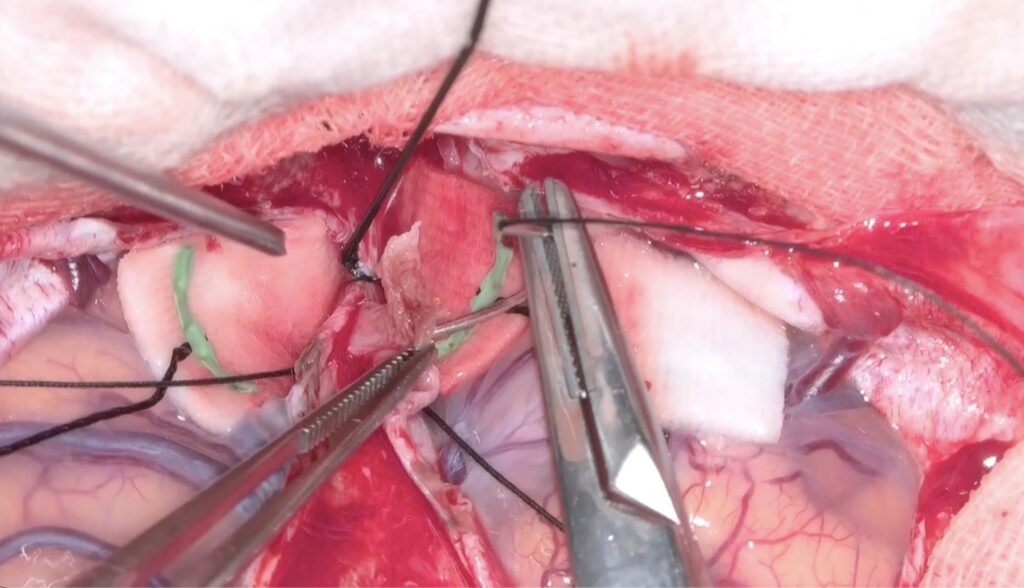

右嗅神経を剥離固定して右前頭葉だけを牽引して大脳半球間裂を剥離。

半球間裂の癒着が少なく、atraumaticに綺麗に開けることができました。